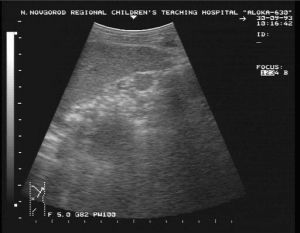

Понятие эхографической синдромологии, или генетического УЗИ, возникло в период активного применения ультразвуковой диагностики в практике МГК беременных.

При ретроспективном анализе предварительного ЭИ или прицельном контрольном исследовании плода с выявленным хромосомным или генным синдромом отмечали характерные особенности и аномалии развития.

На протяжении многих лет в научной литературе накапливались описания различных пороков развития и фенотипических особенностей, характерных для генетических заболеваний, получивших название эхографические маркеры. В результате на основании специфического сочетания отдельных эхографических маркеров сформировался эхографический синдромокомплекс наиболее частых врожденных заболеваний.

Затем при внедрении скрининг-УЗИ в стандарт обследования беременных выявление эхографических маркеров ВНЗ стало показанием для направления беременной на экспертное синдромологическое (генетическое) ЭИ и консультацию генетика.

Выявление эхографического синдромокомплекса при проведении экспертного синдромологического ЭИ в совокупности с заключением генетика — показание для решения вопроса о кариотипировании или специфическом генетическом обследовании плода.

Эхографическими маркерами врожденной патологии могут быть как анатомические аномалии, так и особенности развития плода, не относящиеся к анатомическим дефектам, а также особенности плаценты, пуповины и аномальное количество околоплодных вод.

Наиболее характерные эхографические признаки описаны при часто возникающих синдромах. Однако даже выраженная триада маркеров не позволяет ставить диагноз только на основании ЭИ, без проведения специальных лабораторных методов. Выявление при скрининговом ЭИ эхографических маркеров ВНЗ — показание для направление пациентки для проведения экспертного синдромологического ЭИ.